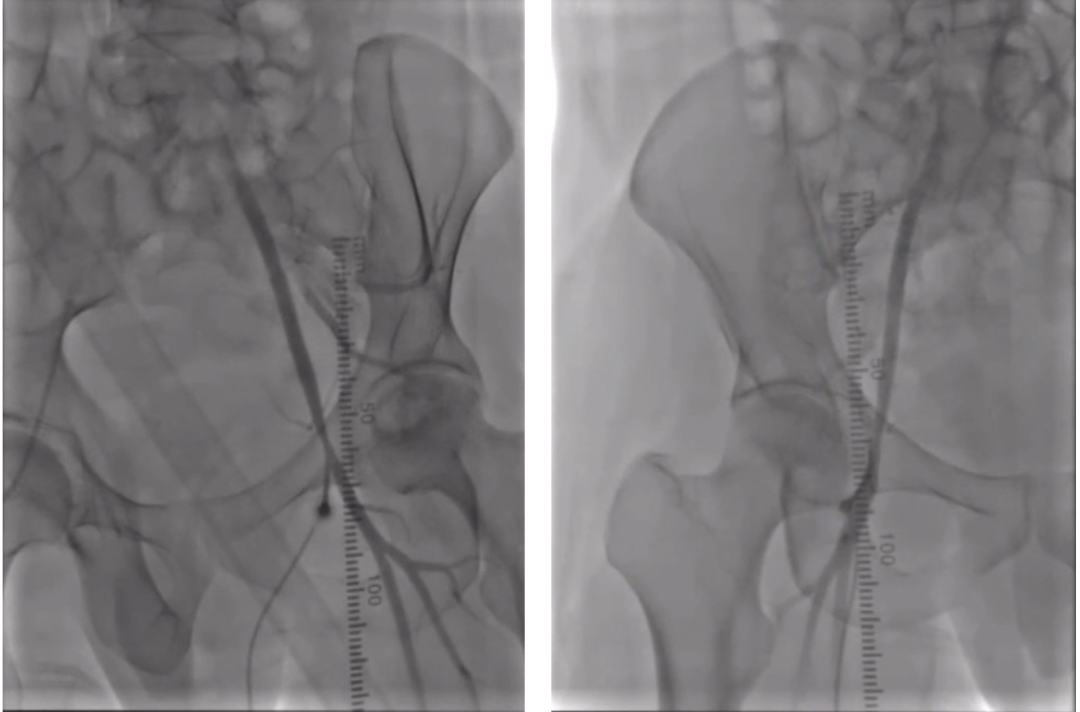

双侧股动脉入路,右侧预置Perclose Proglide(支架入路),左侧6F 55cm长鞘,造影定位;

腹主动脉假性动脉瘤(Medtronic cuff 23mm×23mm×45mm)近端平齐左肾动脉下缘,远端保留肠系膜下动脉;